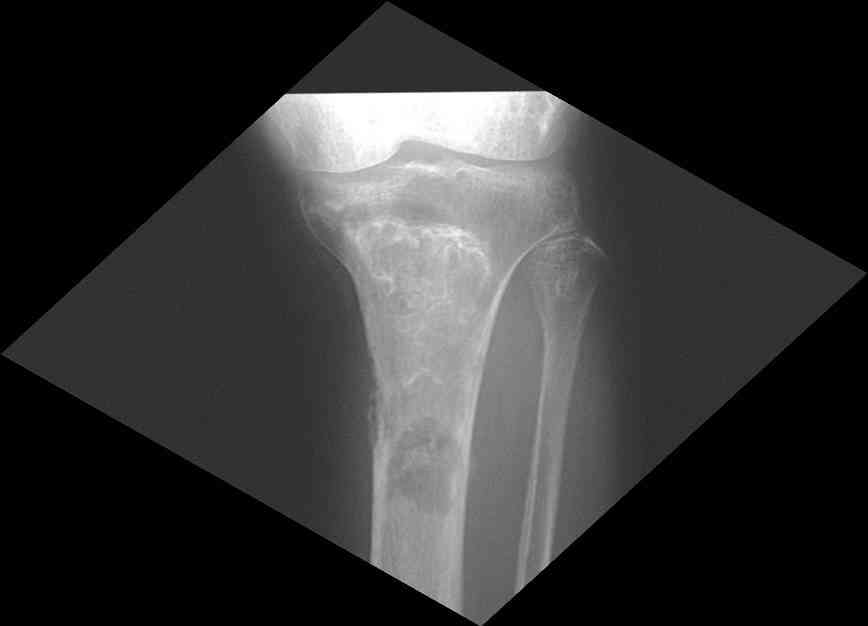

Мужчина, 53 года, жалуется на постоянные ноющие боли в костях голеней, усиливающиеся после ходьбы, боли в коленных суставах. Считает себя больным с 1987 г., когда впервые появились боли в коленных суставах. В 1990 г. выставлен д-з: вторичный ДОА коленных суставов, фиброзная дисплазия костей. После проведенного лечения (НПВП, радоновые ванны, курс введения кислорода в коленные суставы) в течение 5 лет ремиссия. С 1995 г. ежегодные обострения весной и осенью, проявляющиеся болями в коленных суставах, явлениями синовита. Проводилось лечение НПВП, физиопроцедуры, внутрисуставное введение дипроспана с положительным эффектом. С 2004 г. - эффекта от проводимой терапии нет. В 2006 г. впервые по рентгеновским снимкам выставлен д-з: болезнь Альберса-Шенберга. Деформирующий гонартроз справа 2 ст., слева 3 ст. С 2006 г. ездит на лечение в Китай, где проводится лечение радоновыми грязями, массаж с положительным эффектом. Объективно: коленные суставы деформированы, при пальпации б/болезненные. Движения в полном объеме. При ходьбе хромает. Диагноз: болезнь Алберс-Шонберга. Деформирующий гонартроз справа 2 ст., слева 3 ст.Хотелось бы уточнить диагноз и определить тактику дальнейшего лечения. Заранее спасибо.

Представленные Вами данные о пациенте 57 дет с болезнью Альбертс-Шенберга чрезвычайно интересны, но диагноз вызывает большие сомнения. Для мраморной болезни характерно прееобладание склероза, а на представленных рентгенограммах преобладает симметричная дезорганизация архитектоники губчатой кости в эпиметафизарной зоне дистальных отделов бедер и голеней.

Мне кажется, представленные рентгенограммы скорее соответствуют варианту фиброзной дисплазии который был описан М. Campanacci (1976) или

обызвествляющей фиброме H.E.Schlitter (1958).

Уважаемый Константин Иванович! Полностью согласен с проф. Михайловым, данный случай не похож на мраморную болезнь, при которой имеется резкое, строго симметричное и генерализованное уплотнение костной ткани (остеопетроз), и кость оказывается построенной преимущественно из гомогенного компактного костного вещества. Для примера привожу случай из архива нашего института (бедренные, плечевые кости и таз, рис 1,2,3)

Изменения структуры костей у Вашего пациента больше похожи на полиоссальную форму фиброзной дисплазии или болезнь Педжета, возможены также инфаркты костного мозга б.берцовых костей. К сожалению, качество снимка не очень хорошее, непонятно, сохранен ли кортикальный слой б.берцовых костей по передней поверхности.

Не являюсь специалистом по костной патологии, но мне кажется, на ренгенограмме множественные мета-диафизарные образования напоминяющее змееподобных извилистых линии и периостеальные ламинирование очень напоминяет картину остеонекроза (инфаркта) костей, возможно связано с длительным применением стероидов.